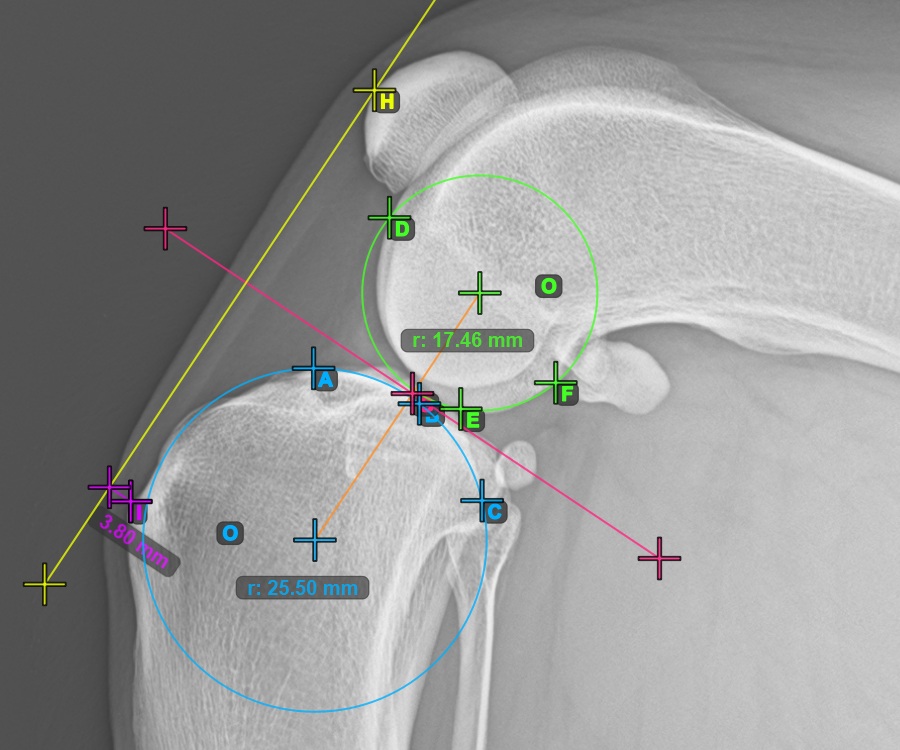

Start the TTA measurement procedure by marking the most cranial point of the Patella.

The image below depicts the usual placement of the most cranial point of the Patella.

To complete the TTA - 1 Condylus variant of TTA measurement procedure mark the most dorsal point of the Crista Tibiae (Tuberositas Tibiae). The distance between the Tuberositas Tibiae and the line passing along the most cranial point of the Patella is the required adjustment for the TTA procedure.

The image below depicts the usual placement of the tibial tuberosity, the most prominent point of the tibial crest.